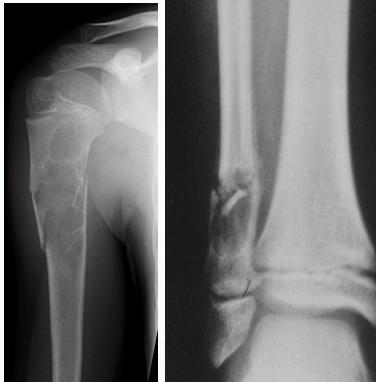

Simple Bone Cyst

- Solitary – unicameral

- Children

- Metaphysis:

- Prox. Humerus and Femur

- Not a tumor:

- Not seen in adults

- Heals spontaneously

- Pathological fracture / or incidental

- Aspirate is clear straw-colored

Aneurysmal Bone Cyst

- Child - young adult

- Metaphysis of long bone

- X-ray:

- Well-defined cyst

- Trabeculated

- Eccentrically placed

- Ballooning

- Bloody content

Comparison of Cyst-Like Lesions in Bone

- Fills medullary cavity

- Does not expand bone

- At metaphyseal side of physis

- Expansile

Giant-Cell Tumor

- After fusion of physis

- Extend to sub-articular